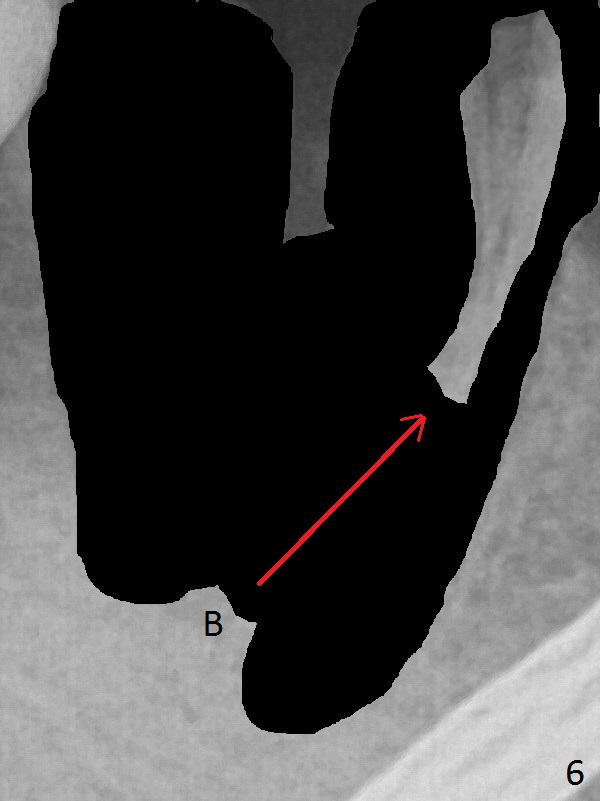

A 43-year-old man has residual roots at #30 (Fig.1). The mesial (M) and distal (D) roots approximates each other so close that the septum is thin (Fig.1,3-5). The latter is unfavorable for osteotomy. After extraction (Fig.5), the middle of the septum (Fig.8a (axial section of the sockets)) will be sectioned (Fig.6, 8b,c) prior to initial osteotomy (Fig.7,8d). The depth of the latter will be ~ 5 mm (Fig.2 red line) for a 13 mm (pink line) IBS implant.